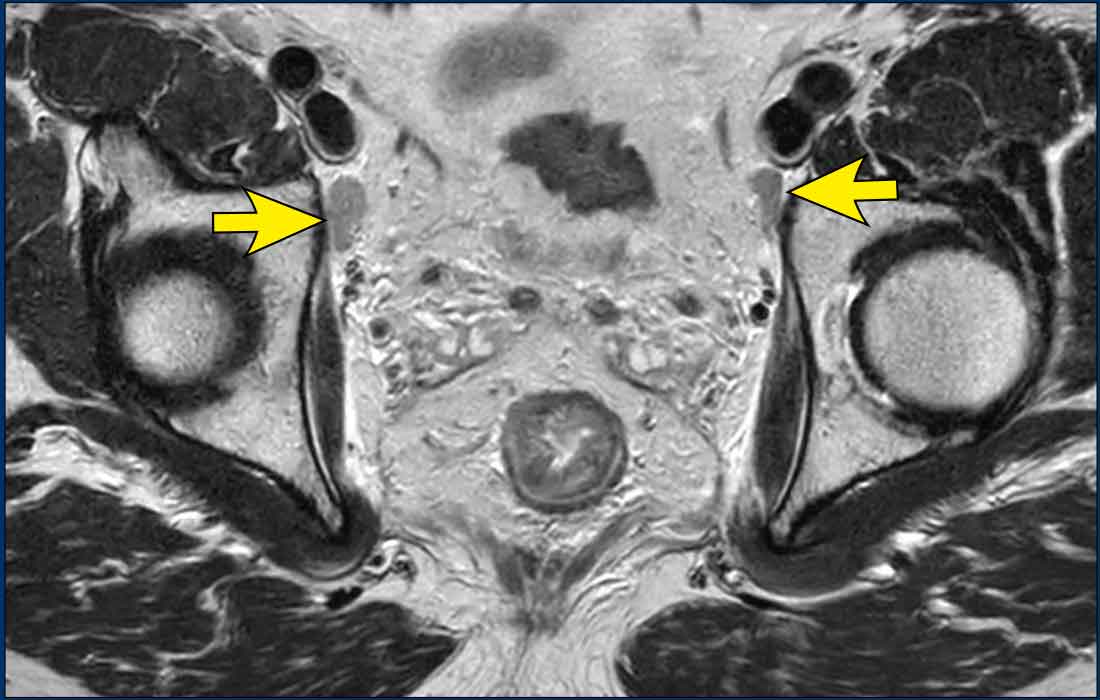

Images

• Left image: Pathologic 9 mm lymph node in the left obturator space (arrow), identified at baseline staging. Requires irradiation and/or separate resection to avoid lateral recurrence.

• Right image: Patient treated with standard TME (without lateral nodal resection) who developed an irregular mass in the left obturator space, consistent with lateral nodal recurrence.